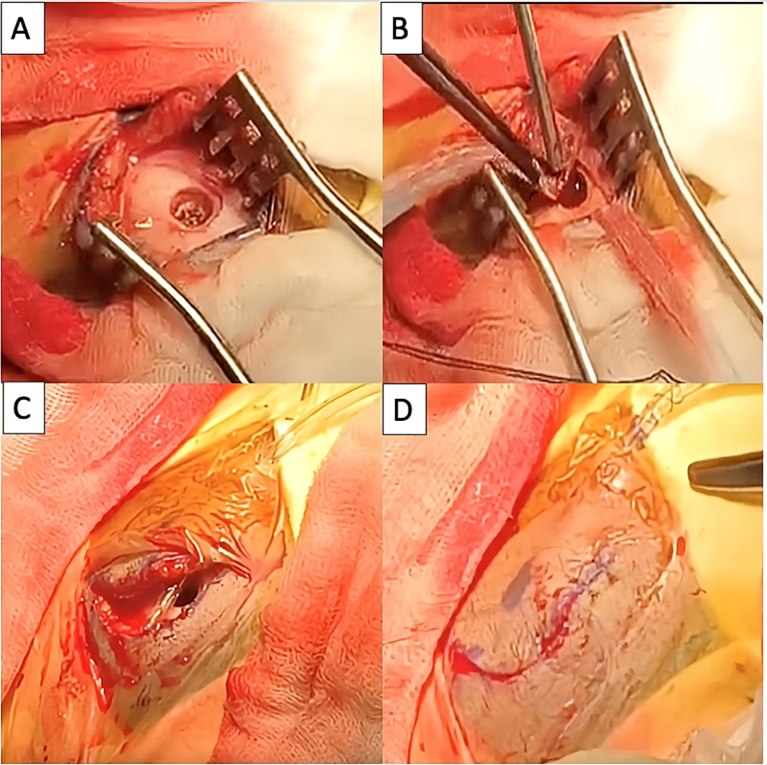

Hình 3. Hình ảnh trong mổ lấy máu tụ mạn tính bằng phương pháp Burr-hole bán cầu não trái (A-D)